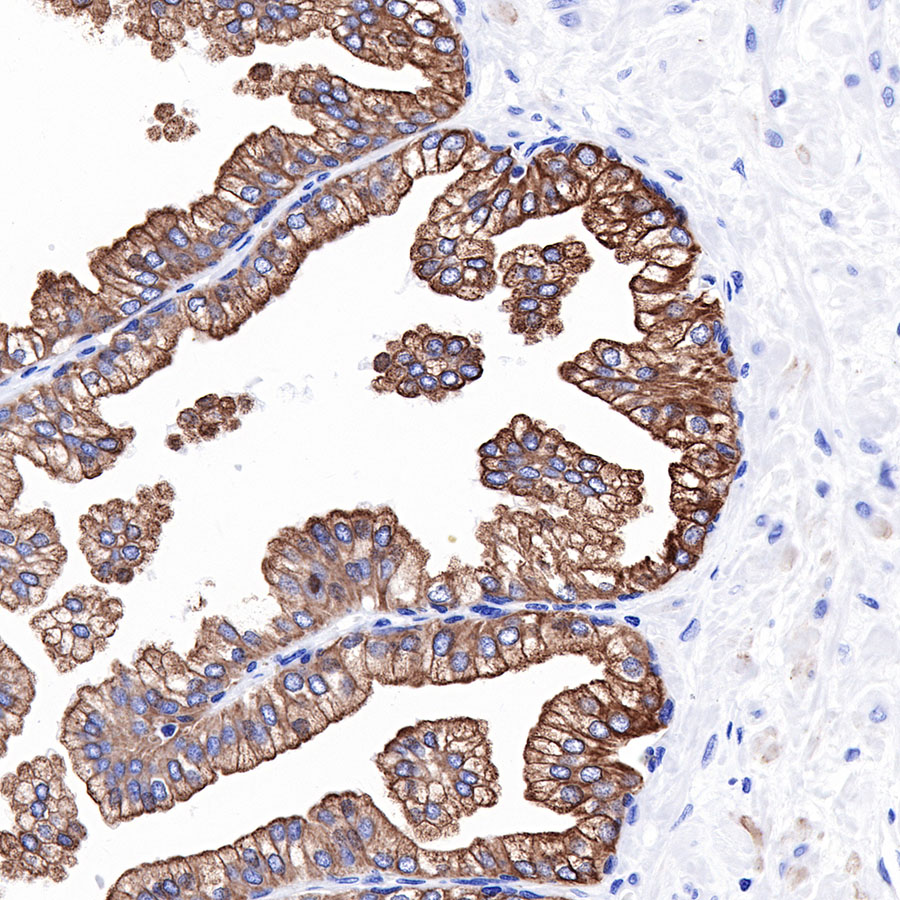

| IHC-P |

1:2000 |

Background

Cytokeratins are proteins of cytoskeletal intermediate filaments, and their main function is to enable cells to withstand mechanical stress. In humans, 20 different cytokeratin isotypes have been identified. Cytokeratins 8, 18, 19, and 20 have been associated with bladder. Cytokeratin 18 (KRT18, also called K18), found in epithelial cells, is released from hepatocytes upon death.